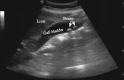

Figure 2

Pericardial effusion.